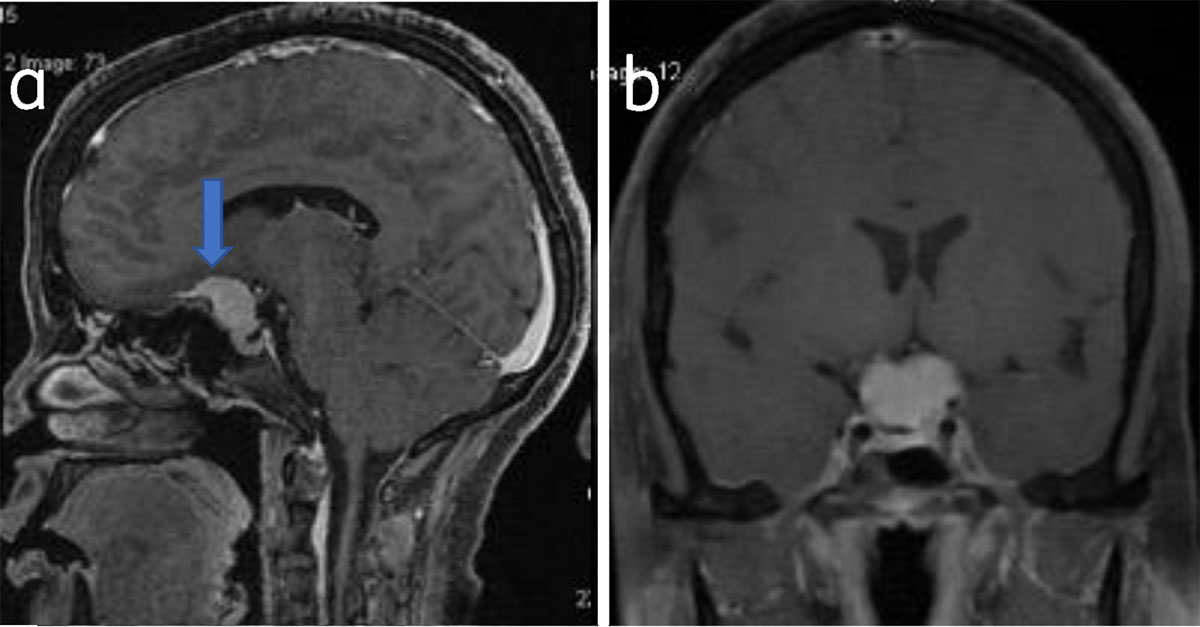

Common locations include parasagittal, convexity, and sphenoid wing. Uncommon locations include olfactory groove, optic nerve sheath, intraventricular, tentorial apex, and intraosseous and posterior fossa (Figures 4, 5, 6, 7, 8).

Figure 4

Suprasellar meningioma: Sagittal (a) and coronal (b) post-contrast T1W shows suprasellar meningioma (arrow).